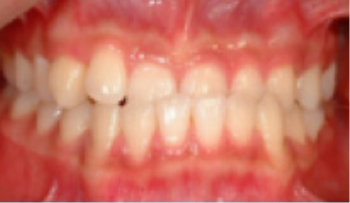

• 과개 교합 아랫니와 윗니가 깊게 물려 아래 앞니가 잘 안 보임.

Before

After